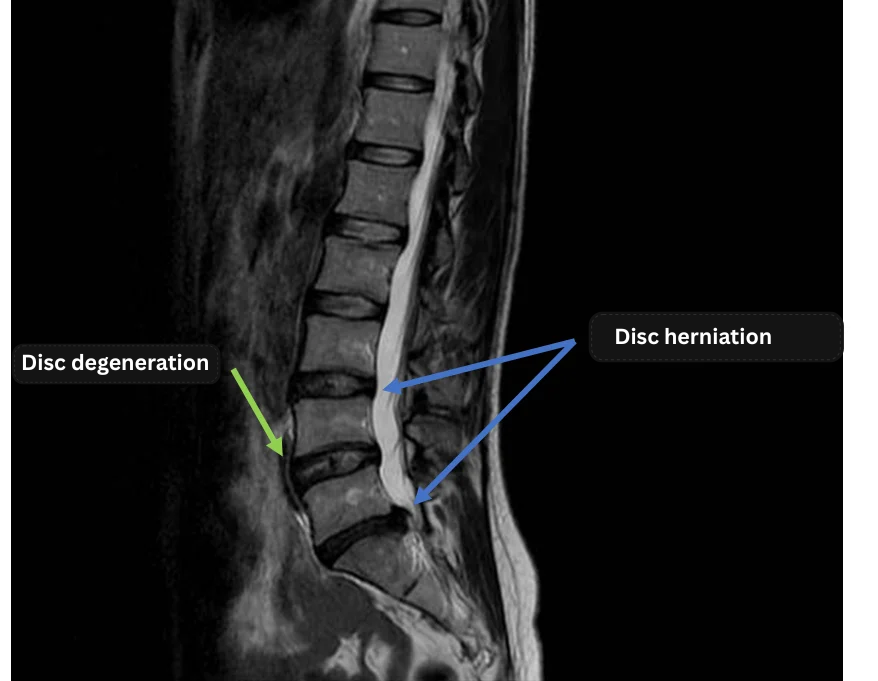

Imaging and findings

- Disc herniation was observed at three levels: L3/4, L4/5, and L5/S.